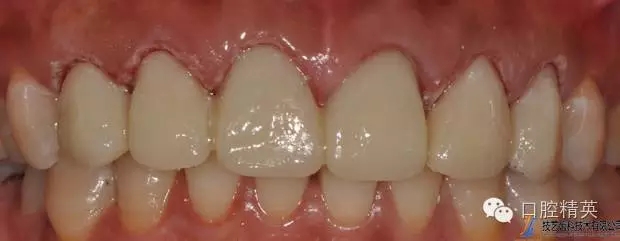

修復(fù)體完成后正面觀

修復(fù)體完成口內(nèi)照片